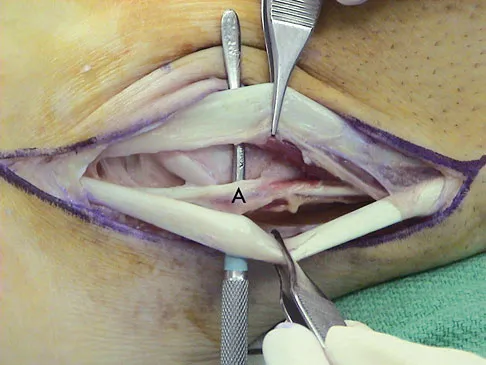

A 40-year-old man has a painful mass on his anterior ankle joint with limited range of motion. A radiograph, MRI scan, a gross specimen, and a hematoxylin/eosin biopsy specimen are shown in Figures 5a through 5d. What is the most likely diagnosis?

Explanation